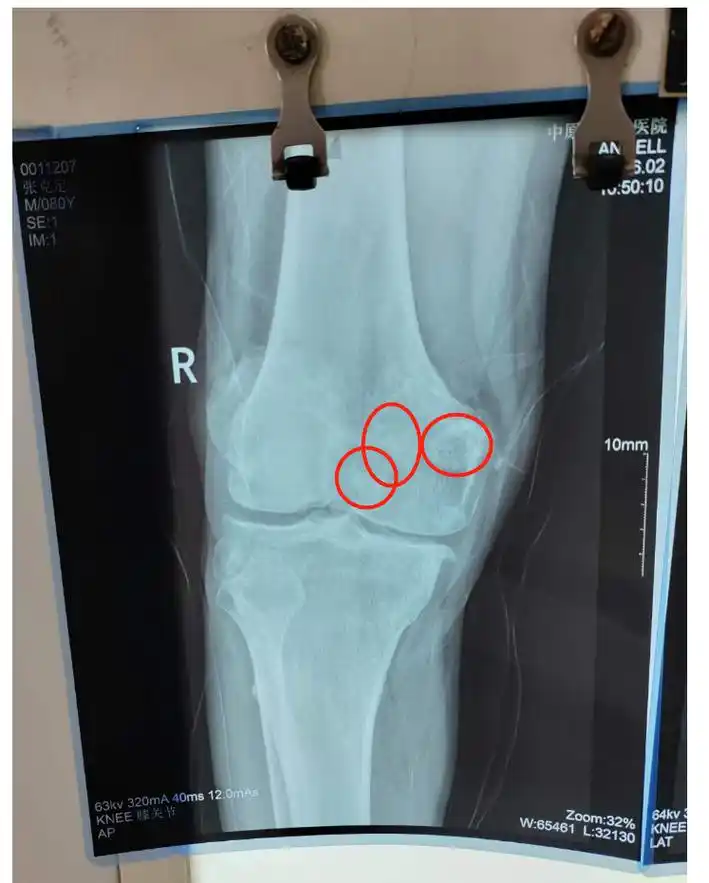

小心出现这些症状可能是关节鼠在作怪

在当地医院做了x线检查, 当地医生发现 王师傅的膝关节里密密麻麻的

走不成路,"关节鼠"在作怪